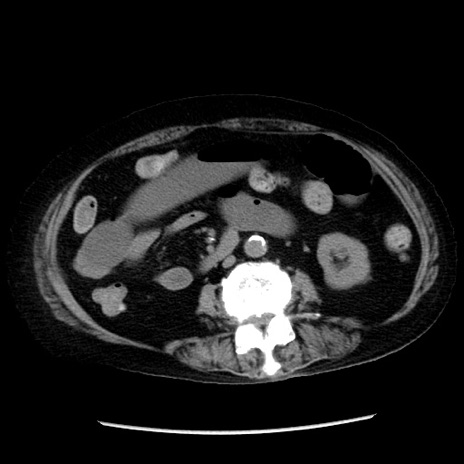

症例14(横断像)

【症例】 90歳代女性

【主訴】 腹痛・嘔吐

【現病歴】今朝から左側腹部痛を認めた。 経過観察していたが、嘔吐を認めたため来院。

【既往歴】 子宮癌術後

【身体所見】 意識清明、BP 127/54mmHg、P 98bpm Sp02 95%(RA)、BT 35.8°C、腹部平坦・軟腸ぜん動音聴取良好、右下腹部圧痛(+) 反跳痛なし

【データ】WBC 9800、CRP 0.46